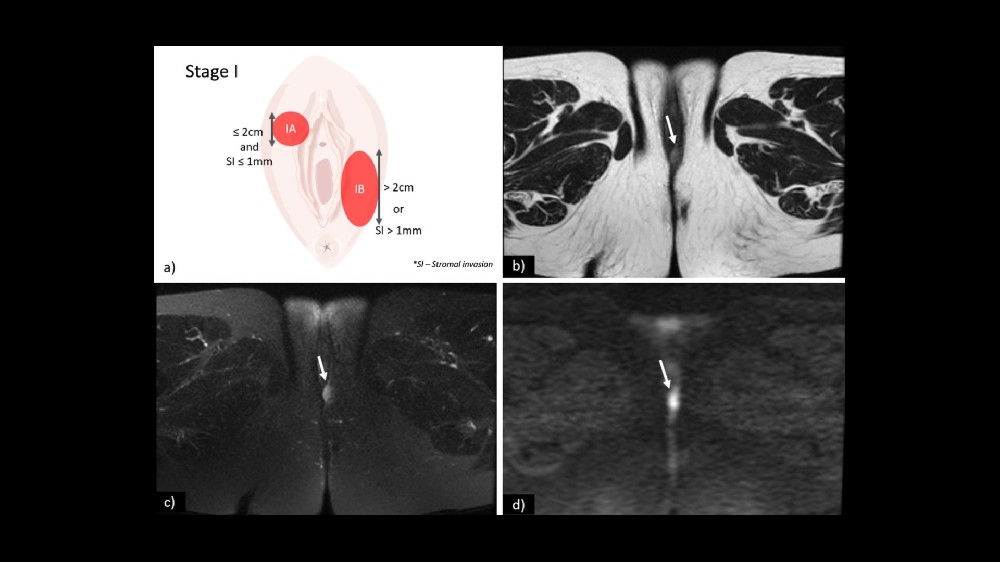

第 1 期 - 外陰癌 (Vulvar Carcinoma)

在第一階段,腫瘤完全位於外陰,直徑通常小於 2 公分。

腫瘤局限於外陰皮膚或下層組織。

未發現淋巴結受累或遠端擴散。

治療選擇:手術切除、放射線治療,以及結合代謝腫瘤學的綜合方法。

結果:五年內的存活率超過 90%,強調早期發現的意義。